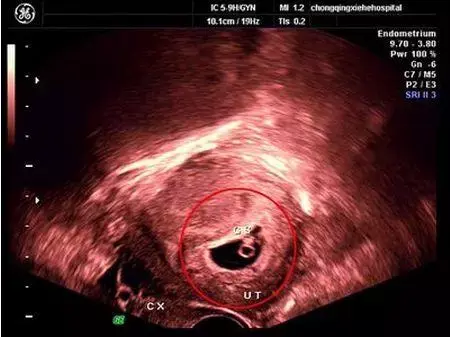

胎囊也叫孕囊或者妊娠囊,是胚胎最初的形态,将来宝宝就从这里长出来。 胎囊形成时间:孕30~40天。 一般月经比较正常的女性,停经35天 (孕5周)左右,通过B超就可以看到胎囊;孕6周时,孕囊的检出率为100%。 胎囊大小与孕周是相对应的,医生通常是通过B超检查的 孕囊大小 来推算孕周,这要比根据末次月经时间推算要准确。 1、异常胎囊 位置异常: 健康的胎囊应该在 卵黄囊内径一般在 35 mm,妊娠第 510 周逐渐增大,而 10 周之后逐渐减小。 卵黄囊的数量可用以判断多胎妊娠的羊膜囊性。通常来说,胚胎存活时卵黄囊数量与羊膜囊数量一致。因此,单绒单羊妊娠时可表现为 2 个胚胎、1 个绒毛膜囊、1 个羊膜囊和 1 个卵黄囊。孕囊大小对照表 怀孕4周:胎儿0.2厘米,此时的胎儿体积非常的小,用b超是看不到痕迹的。 怀孕5周:胎儿0.4厘米,通过b超可以看见胎囊,也或许可以看到胎芽。 怀孕6周:胎儿0.85厘米,通过b超可以看清楚胎囊,也可以看见胎芽及胎心跳。

怀孕4周,胎儿已经开始在你的身体里孕育了。 这个时候或许你还感觉不到,但也有部分准妈妈开始出现 早孕反应 ,比如全身乏力,体温上升等。 但如果出现孕早期阴道流血,并且有轻微腹痛和腰痛的话,要怀孕六周,正常胎囊大小应该是多少 : B超检查只能在妊娠5周后可以看见孕囊,妊娠6周时妊娠囊检出率达100%妊娠6—7周可见胚芽,孕49天,胚芽径线2mm时可见原始心管搏动,妊娠8周初具人形 过早做B超,是不容易见孕囊的影子,太小了患者信息:女 25岁 吉林 长春 病情描述(发病时间、主要症状等): 子宫前位,54*58*42cm,宫内可见24*17cm的胎囊,其内未见明显胎芽,胎囊周围回声欠均匀。